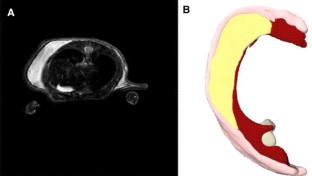

Cryopreservation of subcutaneous white adipose tissue (sWAT) avoids multiple surgeries in patients subjected to reconstructive procedure. Fat grafts were performed subcutaneously on 26 mice treated with fresh (13 mice) or cryopreserved (13 mice) human sWAT. Cytofluorometry for CD marker expression of stem cells, differentiation capability, and in vivo survival of fat grafts were evaluated. In vitro analysis evidenced that cryopreservation did not affect the stem potential of samples. In vivo MRI showed that grafts were well preserved in 13 mice treated with fresh sWAT, whereas in 13 animals treated with thawed fat, graft volumes were strongly reduced after 1 week. Ultrastructural studies performed both on fresh and thawed specimens demonstrated that grafts performed with thawed sWAT are able to store lipids more slowly with respect to grafts performed with fresh sWAT and adipocytes maintained a multilocular appearance. Collected data demonstrated that the protocol of cryopreservation could maintain the regenerative capability of the sWAT, but the rate of reabsorption after fat grafting is higher using cryopreserved sWAT. Maintaining the stem potential of sWAT after cryopreservation is a very important aspect for reconstructive and regenerative medicine. The employment of cryopreserved sWAT represents an interesting goal for surgeons. Surely there is the necessity to improve the protocol of cryopreservation.